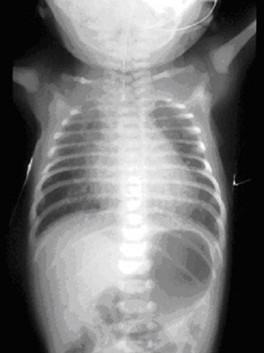

Diagnostique

prenatale est difficile

:Grossese hydramios ++ , Estomac non vue ( Type I,II ) ,avec

des autres malformations . A salle de

naissance , une cliche de face thoraco-abdominale et

cliche cervico-thoracique de profile avec sonde radio-opaque

butee en oesophage . La trajet du sonde se donne la cite de

atresia ou non ou bien en presente la fistule

tracheo-oesophagienne

Image

radiologique de atresia congenitale de type I . La

contrast arrete a D4 sur la bifurcation de

trachee |

|

Un sonde radio-opaque bute dans oesophage

se donne la cite de atresia . Cliche

thoracoabdominale de face . |